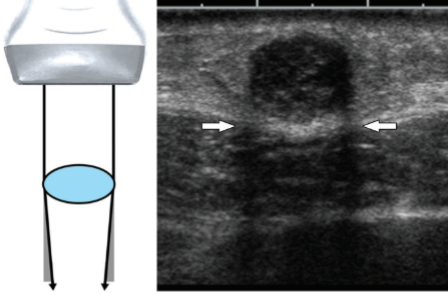

Slice (Section) Thickness

AKA Partial Volume Filling

Beam is too thick in the elevation plane

Gives the appearance of debris in an echo-free structure

Partial Volume Filling, thick, elevational, echo-free

Slice (Section) Thickness Artifact

AKA ___ ___ ___

Beam is too ___ in the ___ plane

Gives the appearance of debris in an ___ structure